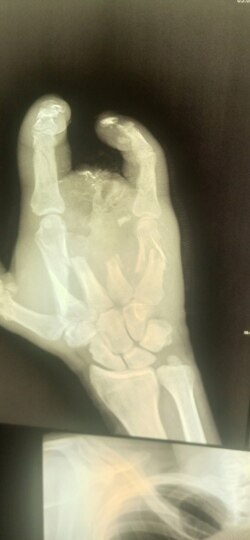

Рука Алексея после ранения на войне

Оказалось, что с незажившими ранами покалеченного солдата отправили в гражданское медучредждение для того, чтобы на руках у него не было документов из военного госпиталя. И сейчас Алексей не может доказать, что стал калекой в бою.

– Прописали мази и перевязки. Я засомневался, что лечение нормальное, благо, был знакомый хирург. Я пришел к нему и очень вовремя – началось загноение на обрубке руки. Там он уже сделал все заново – чистка, вставил спицы и даже часть кости восстановить смог. Конечно, все за деньги. Всю "зарплату", что получил за войну, считай, все на хирурга и ушло! В итоге вышел "в минус", – подытоживает Алексей.

Протез Алексей пытается получить с начала 2023 года.

– Из ведомств вообще мне не отвечают. Родная часть, в которой контракт заключал, нагло отвечает, что доказывать "боевой характер" ранения должны не они, а "на месте". Тогда, мол, и протез самый лучший получу. И все-все-все. Я, б**ть, туда бы и поехал, и за свои, но по телефонам и полевой, и военный госпиталь меня тоже на*** шлют, – говорит Алексей. – И я, кстати, видел, какие протезы они дают другим раненым – палки с культей. Такой вот "бионах**протез"! Я просто в шоке от отношения. Когда нас заманивали – такая реклама была, мама не горюй! Случись что, мы тебя на руках носить будем – вот такое складывалось впечатление. А сейчас…